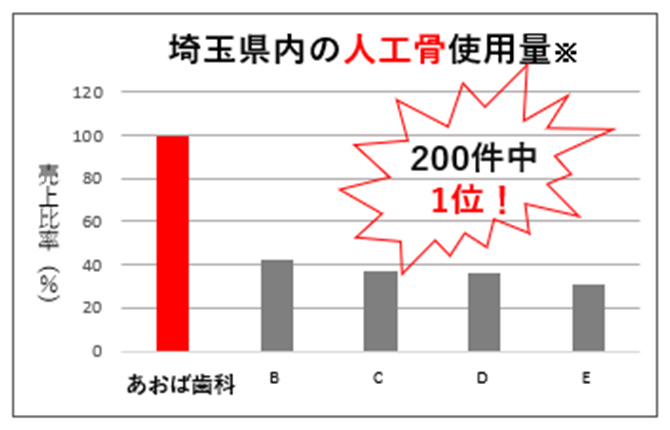

埼玉県内で

昨年も高い

再生医療実績(2025年)